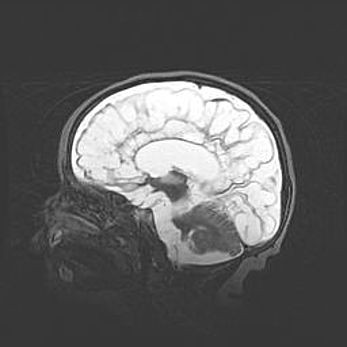

Лейкомаляция с кистозно-глиозной дегенерацией головного мозга.

Возраст: 2 месяца 25 дней

Вес: 6400 г

Окружность головы: 40 см

Срок гестации: 41 неделя

Лейкомаляцию относят к ишемически-гипоксическим повреждениям головного мозга, диагностируемым у новорожденных. При лейкомаляции в головном мозге обнаруживают очаги некроза, возникшие после тяжелой гипоксии и нарушения кровотока. В процессе морфогенеза очаги проходят три стадии: 1) развития некроза, 2) резорбции и 3) формирования глиозного рубца или кисты. Перивентрикулярная лейкомаляция (ПЛ) встречается примерно в 12% случаев среди новорожденных, обычно – у недоношенных детей, причем, частота ее зависит от массы, с которой младенец появился на свет. Наибольшее число малышей страдает лейкомаляцией, если масса при рождении 1500-2500 г.